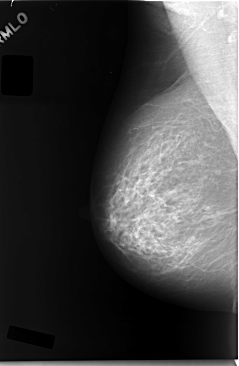

C_0038_1.LEFT_MLO

RIGHT_MLO LINES 5856 PIXELS_PER_LINE 3824 BITS_PER_PIXEL 12 RESOLUTION 50 NON_OVERLAY